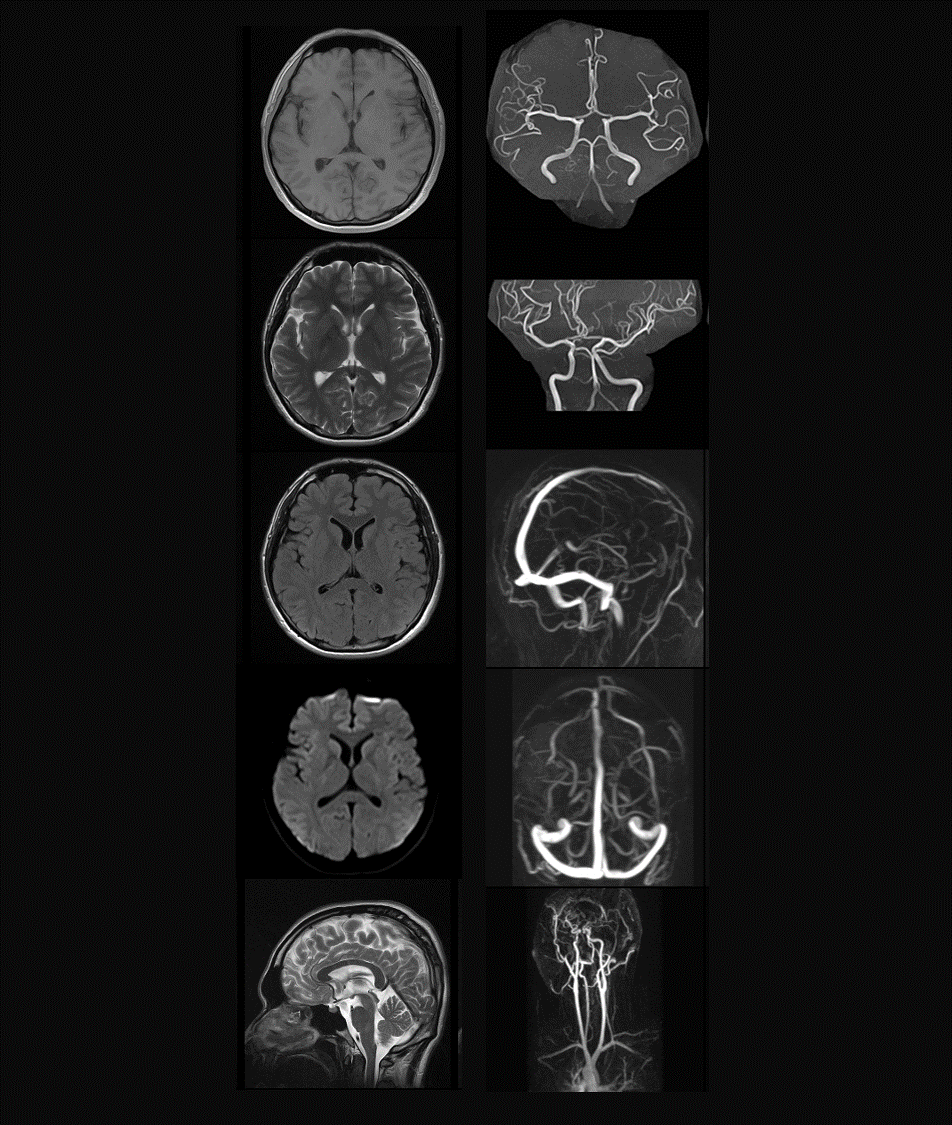

Ò½ÁƿƼ¼ÊÂÒµ²¿Éî¸ûҽѧӰÏñÁìÓò£¬£¬ÒÔAIÊÖÒÕΪ½¹µã£¬£¬´òÔì´ÓÔ­ÖÊÁÏ¡¢¡¢¡¢ÔªÆ÷¼þ¡¢¡¢¡¢ÏµÍ³²¿¼þµ½Ò½ÁÆ×°±¸Õû»úµÄÈ«¹¤ÒµÁ´£¬£¬²úÆ·±»ÆÕ±éÓ¦ÓÃÓÚÒ½ÁÆÓ°Ïñ¡¢¡¢¡¢ÁÙ´²Õï¶Ï¡¢¡¢¡¢Ò½Ñ§¿ÆÑеÈÁìÓò¡£¡£

MR

ÖÐÊàÉñ¾­

ÖÐÊàÉñ¾­-¸ß¼¶ÁÙ´²Ó¦ÓÃ